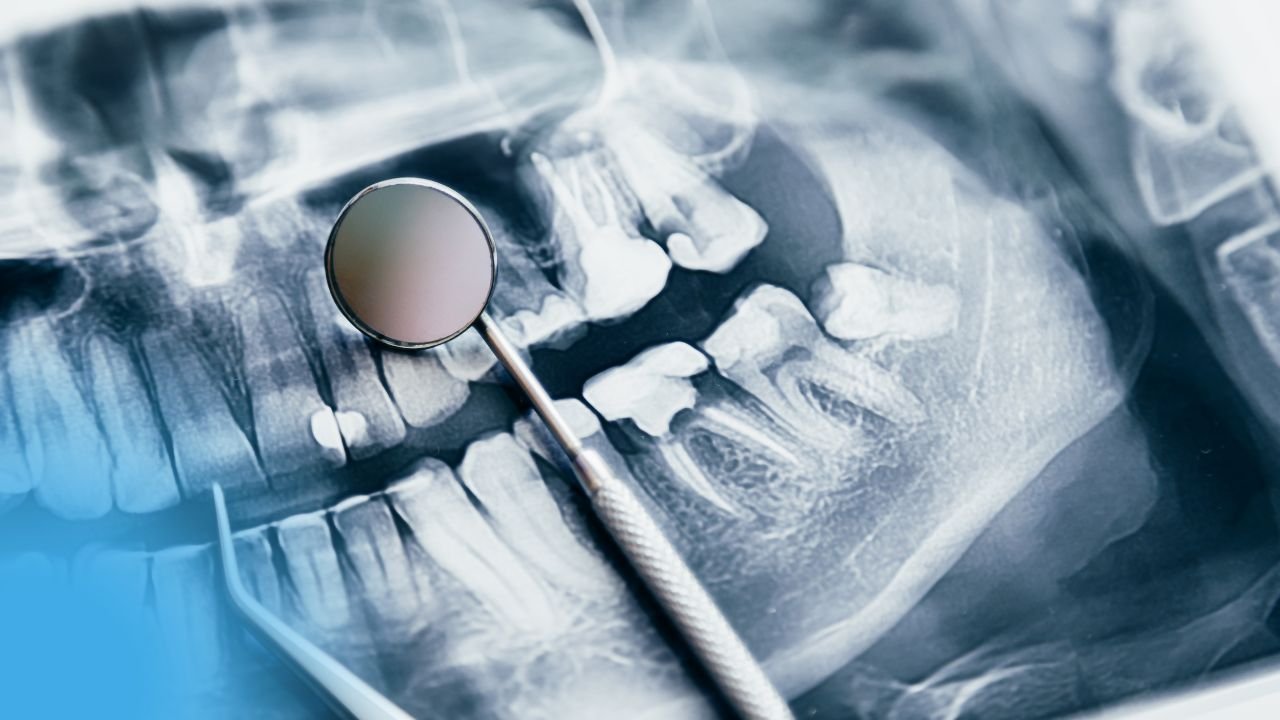

Préparation des Cavités de Classe II, odontologie conservatrice et endodontie

La santé bucco-dentaire est essentielle pour le bien-être général, nécessitant une formation rigoureuse et continue des dentistes. Les étudiants en médecine dentaire doivent maîtriser l’anatomie dentaire et les techniques de diagnostic pour exceller. Les praticiens doivent adopter les nouvelles technologies, comme la radiographie numérique, pour améliorer la précision des soins. La prévention, via l’éducation à l’hygiène buccale, reste la pierre angulaire de la pratique dentaire moderne. Les étudiants doivent se familiariser avec la gestion des urgences dentaires, comme les abcès ou les fractures dentaires. La collaboration interdisciplinaire avec d’autres professionnels de santé optimise la prise en charge des patients complexes. La santé bucco-dentaire est essentielle pour le bien-être général, nécessitant une formation rigoureuse et continue des dentistes.